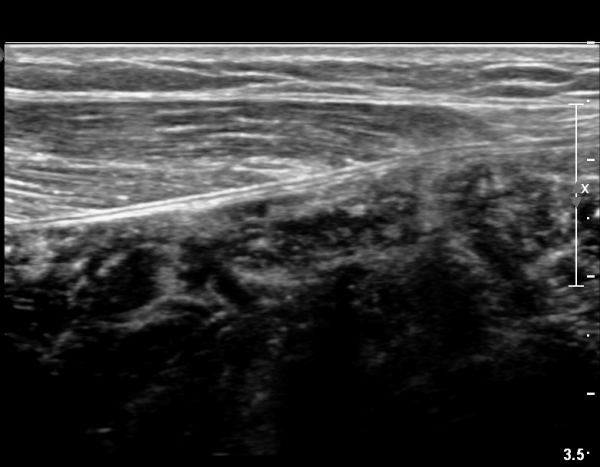

[¹ß¸ñ] simultaneosus tear of GCM and achiles tendon

abrupt leg pain developed during foot volleyball

he walk with severe limping with no weight bearing on rt. leg. on examination, there is local tendernes at GCM and achiles tendon, severe pain with ankle dorsiflexion.

ÃÊÀ½ÆÄ °Ë»ç